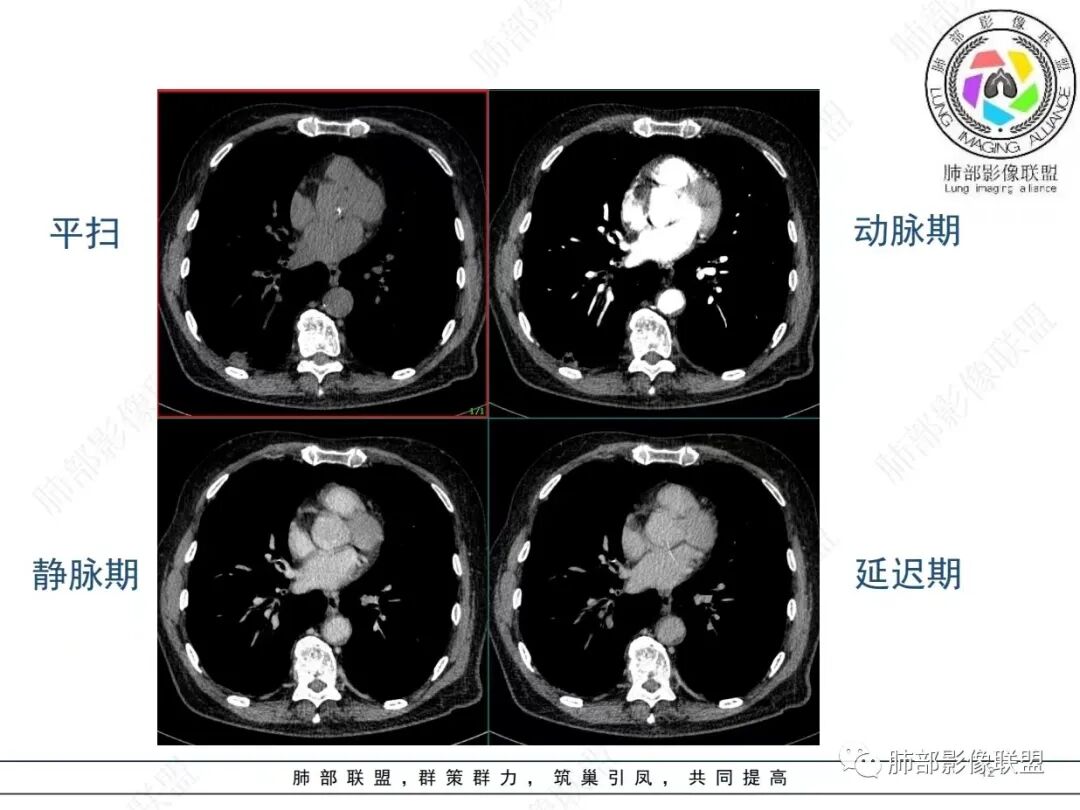

老年男性,发作性气喘,实验室检查白细胞增高。肺部影像表现:右肺胸膜下占位性病变,肺气肿背景,内部可见空腔/空泡影,周围可见小结节,增强动脉期明显强化,静脉期及延迟期强化减低,右侧肺门可见肿大淋巴结,有吸烟史,近年减少,首先考虑恶性肿瘤,肺小细胞癌/鳞癌,隐球菌作为鉴别诊断,病例穿刺活检。

老年男性,气短,胸痛半年,考虑慢性病史,无发热,常见的肺部感染可以排除,右肺下叶基地段靠近胸膜实变影,边缘清楚,不均匀强化,可见空泡征,点状血管影,周围小叶中央型结节,有网格影,支气管扩张,磨玻璃影,肺间质改变,右侧肺门淋巴结肿大,综合考虑恶性肿瘤并肺内转移

老年男性,胸疼入院,影像表现,右肺下叶胸膜下结节,边界清晰,与支气管关系不密切,病灶内见空洞?增强病灶均匀强化,右肺门可见增大淋巴结,考虑恶性病变,小细胞癌,其次鳞癌

老年男性,肺气肿背景,右肺下叶,右肺下叶胸膜处实性结节,形似山丘,有分叶,病灶内可见扩张细支气管/空泡,边缘可见弯曲血管,增强后不均匀强化,可见血管影,病灶胸膜侧呈小波浪??状,局部突入胸膜面,右肺门肿大淋巴结。考虑恶性结节,小细胞肺癌,腺癌,鉴别炎性肉芽肿。建议ct下穿刺活检。

老年男性,肺气肿病史,支气管束增粗,管壁增厚,右肺下叶后基底段胸膜下肿块,土豆征,边界清,有膨隆,小支气管边缘阻断,见集血管束征,肿块强化明显(快进快出特点),并偏心空洞,胸膜下栽赃,周围肺结构破坏(蜂窝状影表现),右肺门淋巴结转移肿大,血管内皮生长因子偏高,肿块与小支气管,血管束关系密切,强化特点,定恶性肺肿瘤,小细胞Ca。

老年男性,肺气肿,右肺下叶胸膜下结节,边缘毛躁,周围多发间质增厚,临近胸膜下脂肪间隙模糊,增强后动脉期不均匀强化,延迟期强化较低,右肺门肿大淋巴结,考虑恶性,鳞癌,小细胞肺癌,鉴别炎性肉芽肿性结节

右肺下叶胸膜下结节,边界清,边缘平直膨隆,血管集束,其内空洞,明显不均匀强化,考虑腺癌?小细胞癌?鉴别隐球菌

肺气肿,胸膜下结节,边界清晰,边缘毛糙,病灶内见空洞,增强病灶均匀强化,右肺门可见增大淋巴结,考虑恶性病变,小细胞癌,其次鳞癌,鉴别隐球

老年男性,肺气肿背景,右肺下叶胸膜下团块影,明显强化,其内空泡征,周边血管聚集,右肺门淋巴结增大,考虑腺癌?

右下叶胸膜下结节,宽基底与胸膜相连,结节与胸膜相交呈钝角〈山丘征〉,内可见充气扩张的支气管,中度强化,结节边缘无毛刺,内见走行自然的血管影,提示破坏力及收缩力差,右肺门可见肿大淋巴结,老年烟民,考虑恶性占位,支持小细胞癌

右肺下叶胸膜下结节,呈山丘状,生长在慢支肺气肿间质纤维化的基础上,边缘相对光滑清晰,右肺门淋巴结肿大,强化呈速升速降,老年男性,吸烟史,考虑小细胞肺癌,鉴别隐球

老年男性,吸烟史40年,肺气肿背景,胸膜下结节,边缘膨隆,增强后结节内有片状坏死区,右肺门及纵隔肿大淋巴结,考虑恶性,鳞癌?小细胞代排

老年患者,右下肺胸膜下结节,有血管聚集、空泡征,强化明显,右肺门见肿大淋巴结。考虑腺癌,鉴别肉芽肿性病变

老年男性,长期抽烟病史,右下肺胸膜下结节,有分叶,胸膜下栽桩,肿块增强可见明显不均匀强化,考虑恶性,鳞癌可能性大,鉴别小细胞肺癌。

恶性明确(右肺门淋巴结明显肿大,中心坏死,坏死边界不清楚,胸膜下馒头样肿块,血管集束,支气管阻塞,动脉期明显强化,内部明确的供血血管提示肿瘤细胞密集,局部坏死边界不清,强化快进快出,邻近胸膜强化呈胸膜尾征,提示胸膜受侵),病理符合周围性低分化鳞癌(老年男性,长期吸烟史,肿块强化明显,快进快出,坏死边界不清楚,阻塞性炎症及阻塞性肺气肿,肺门淋巴结肿大,坏死,邻近支气管壁增厚支持粘膜下侵润生长),白细胞总数高,动脉期强化那么明显,腺癌合并感染倒是要高度警惕。

老年男性,吸烟史+肺气肿背景,右下肺胸膜下肿块(坏死+内部血管影+快进快出),右侧肺门淋巴结肿大,考虑:恶性、鳞?高级别腺待排(总体感觉偏软)。

男,80,发作性气喘半年,加重1天。长年大量吸烟史。肺部CT:肺气肿背景,右肺胸膜下实性占位,处于外周大疱带与气肿带交界,山丘征,边缘膨隆,边界较清,血管集束,周围可见小结节。增强不均匀强化,内可见迂曲模糊血管影,右肺门、隆突下可见肿大淋巴结。首先考虑恶性肿瘤,小?鳞?鉴别PC、TB等。